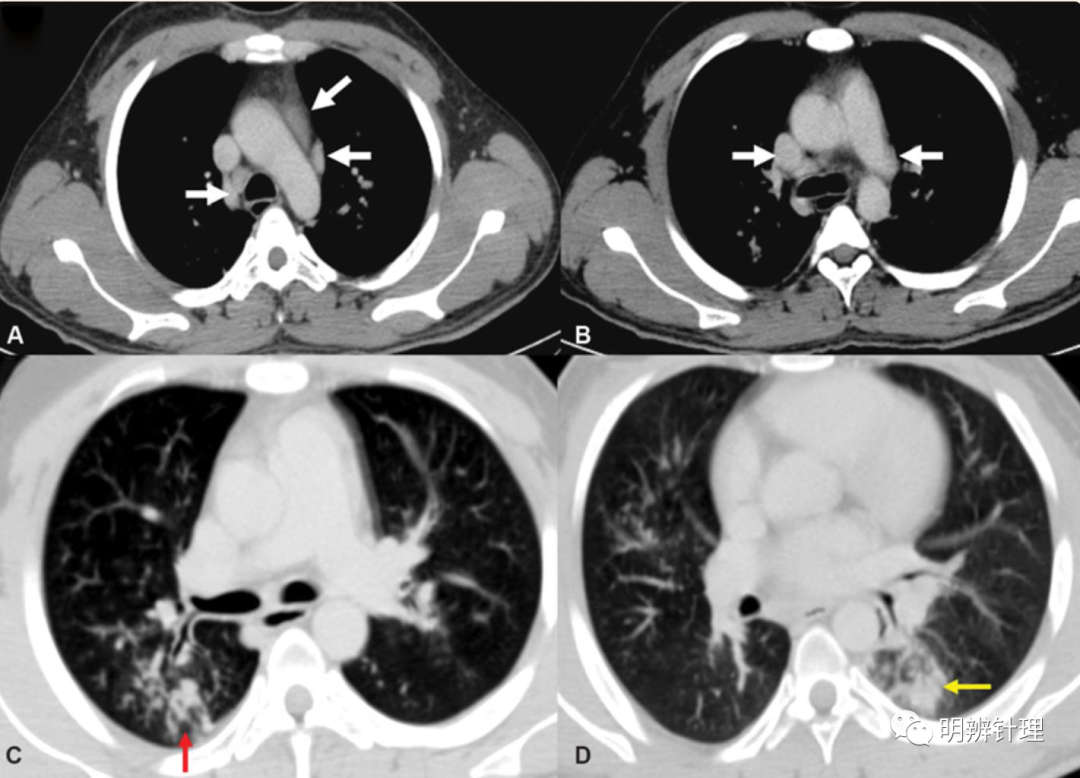

男性,25岁,急性高烧和呼吸窘迫。再生障碍性贫血接受免疫抑制治疗后。增强肺CT,纵隔窗( A、B )显示轻度增强的气管前淋巴结(白色箭头)。肺窗 ( C, D ) 显示右肺(红色箭头)的“树芽征”和左肺的斑片状实变(黄色箭头)。

诊断结果:肺结核